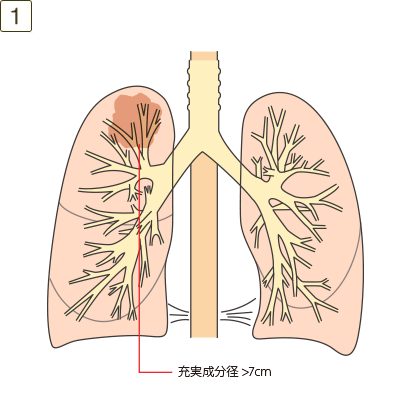

T4

充実成分径>7cm、または大きさを問わず横隔膜、縦隔、心臓、大血管、気管、反回神経、食道、椎体、気管分岐部への浸潤、あるいは同側の異なった肺葉内の副腫瘍結節